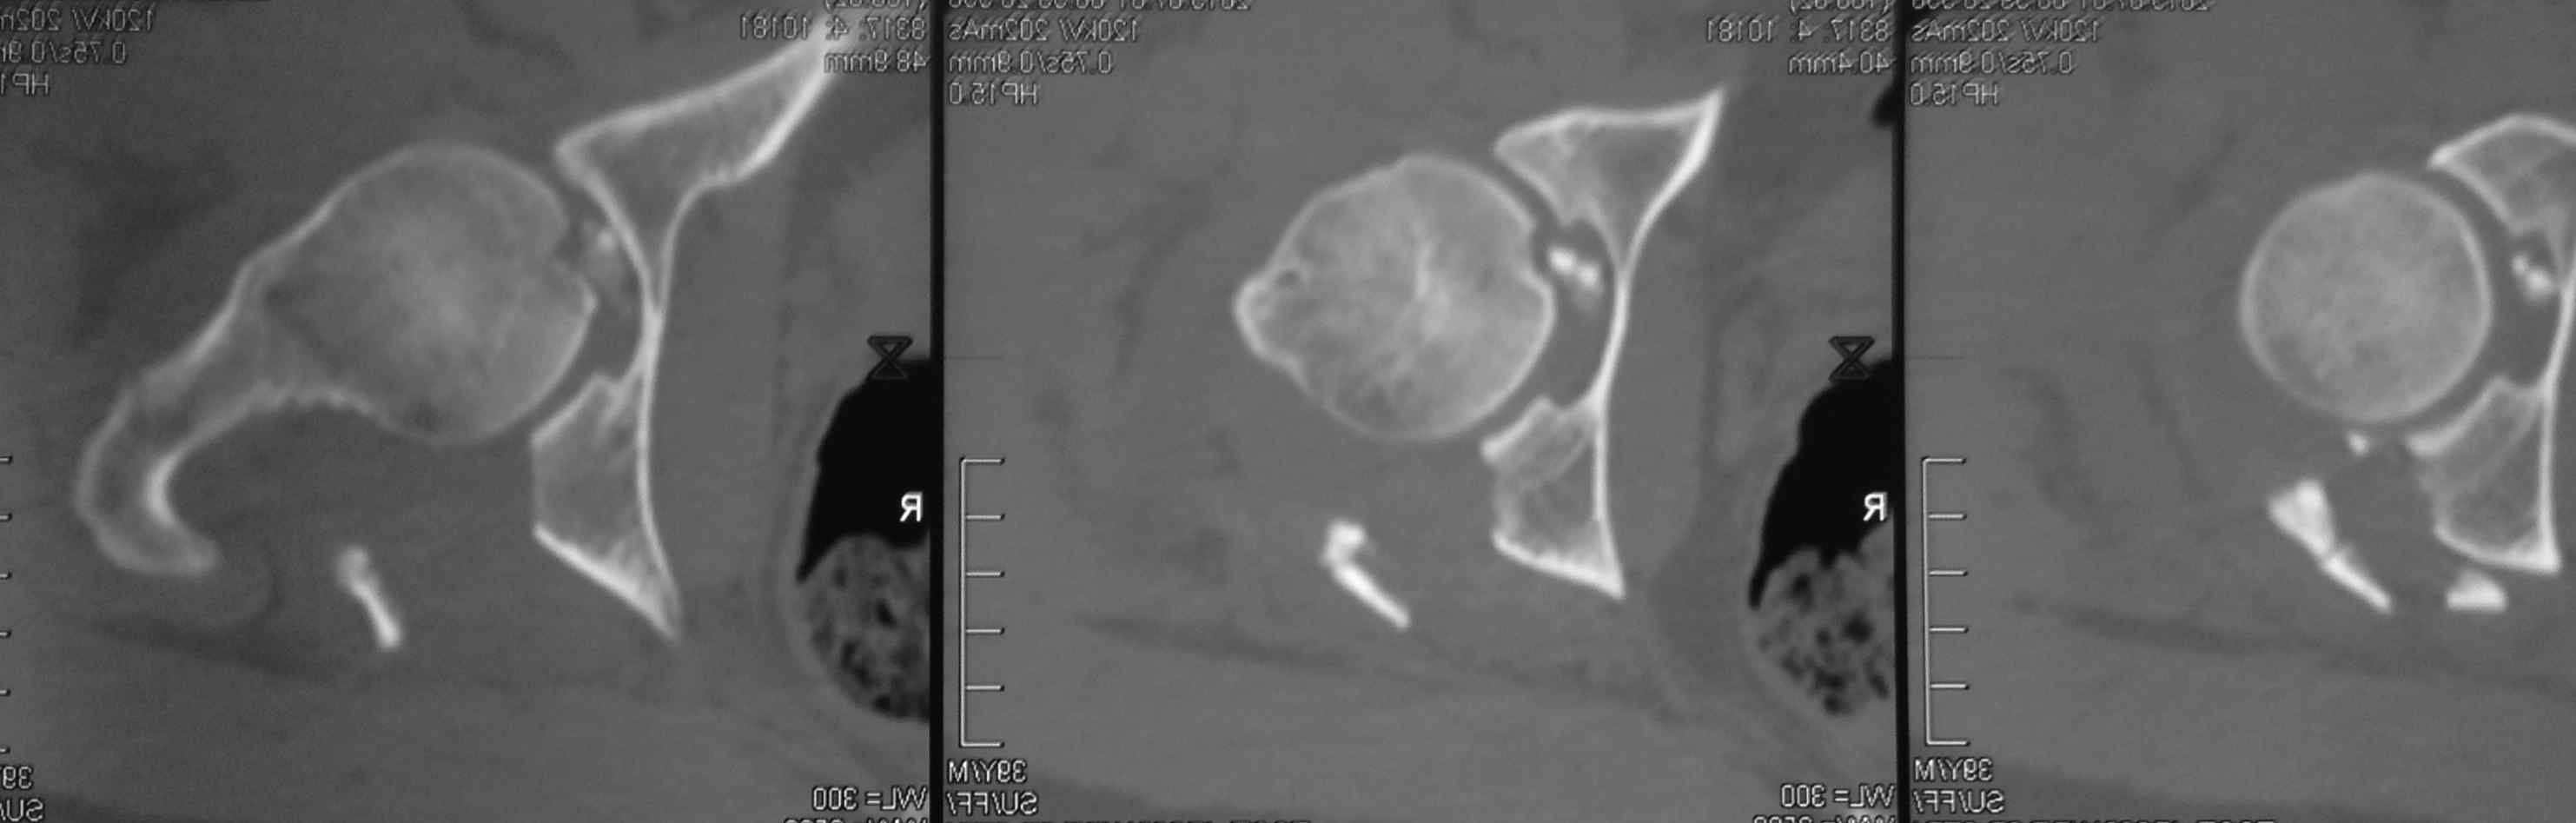

На голени приемлемую репозицию можно сделать закрыто. Фиксация может быть спицами и аппратом или винтами и аппаратом (разгрузка сустава). На бедре для полноценного восстановления функции необходима артротомия и остеосинтез (доступ Кохера, похоже фрагмент заднего края вертлужной впадины).

Фрагмент в полости тазобедренного сустава большой. Мы бы оперировали. В похожем случае, но уже у нас, (см. приложение) внутрисуставной осколок был значительно больше предполагаемого.

Никита, фрагмент в вашем случае несколко в иной локализации и он реально "пережует" впадину, здесь он в ямке.

Добрый день, коллеги! Повреждение вертлужной впадины вероятнее всего 62-А1.2 чистый переломовывих, оскольчатый перелом задней стенки, при этом внутрисуставной фрагмент, является частью артикулирующей поверхности ацетабулюм, а следовательно его необходимо извлечь и поместить на место, иначе мозаика может не собраться. Про FAI временно можно не вспоминать (не до него), поскольку наиболее тяжелое повреждение голени требует адекватного вмешательства.На представленных рентгенограммах таза после операции все отлично, полную картину даст КТ.